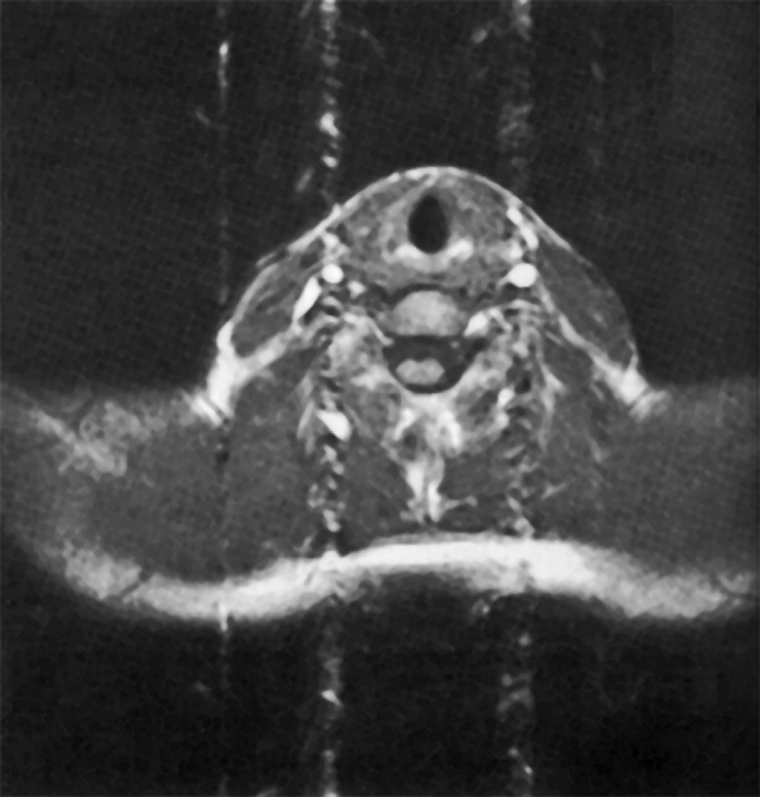

Figura 17-09:

Gradient-echo image of a neck with the pha­se en­coding gradient oriented ver­ti­cal­ly. Flow artifacts are ob­serv­ed as a column associated with arterial ves­sels